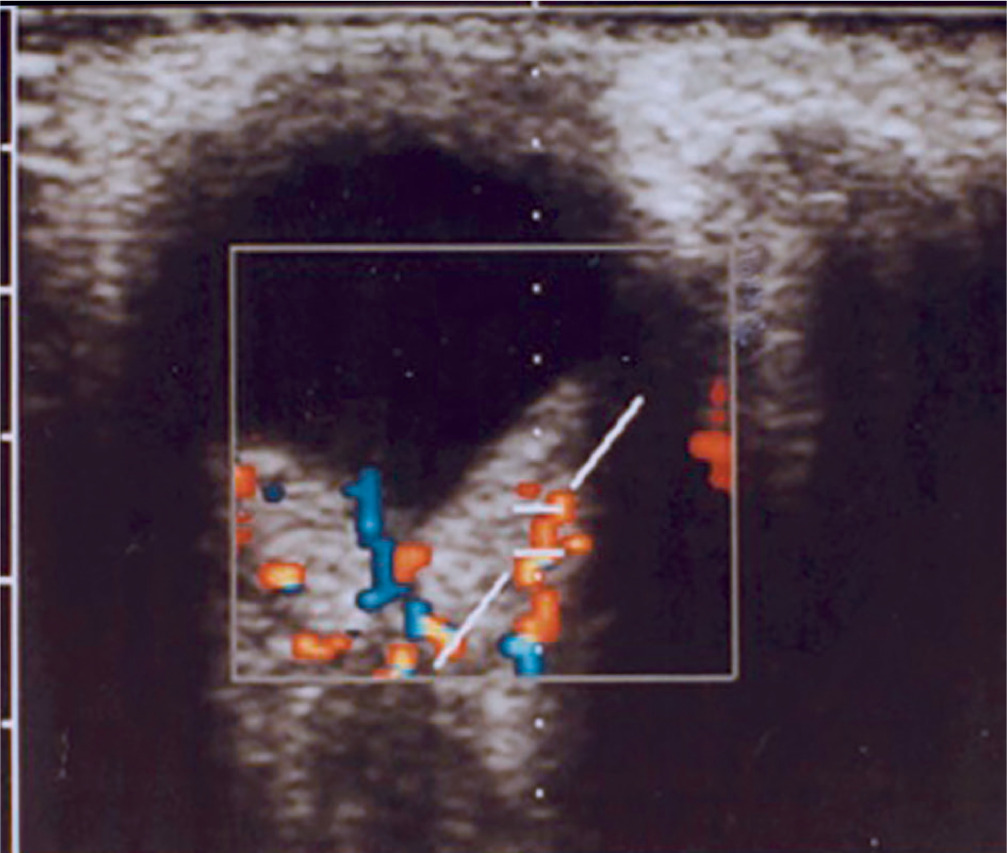

It is a very rare disease, affecting an estimated one in 30,000–40,000 individuals, with around 1,000 cases reported in Poland. The condition is inherited in an autosomal dominant manner. The syndrome is caused by constitutional mutations of the VHL tumor suppressor gene located on the short arm of chromosome 3. Constitutional mutations affecting a single gene are present in all cells of the body and represent the primary cause of pathology in this type of genetic disorder. The syndrome is characterized by the presence of hemangioblastoma-type tumors in the cerebellum, spinal cord, brain, visceral organs, and the eye [16]. The tumors consist of components of hemangioblastomas [6]. Visceral abnormalities are associated with the presence of pancreatic and renal cysts, as well as polycythemia. Tumors such as pheochromocytoma and adenocarcinoma may also occur. Hemangioblastomas that develop in the brain and spinal cord can cause headaches, vomiting, weakness, and loss of muscle coordination (ataxia). Within the ocular globe, capillary malformations affecting the optic nerve and retina are detected. The malformations appear as tumors in both eyes, located peripherally and centrally [6] (Figure 8A, B). Peripheral distribution is characterized by the presence of tortuous, dilated vessels that supply and drain blood from the tumor. In contrast, centrally located vascular tumors typically exhibit an endophytic growth pattern and lack afferent and efferent vessels associated with vascular malformations. Disease progression may lead to retinitis and retinal detachment, iridocyclitis, and rubeosis iridis. The changes may result in the development of secondary glaucoma.